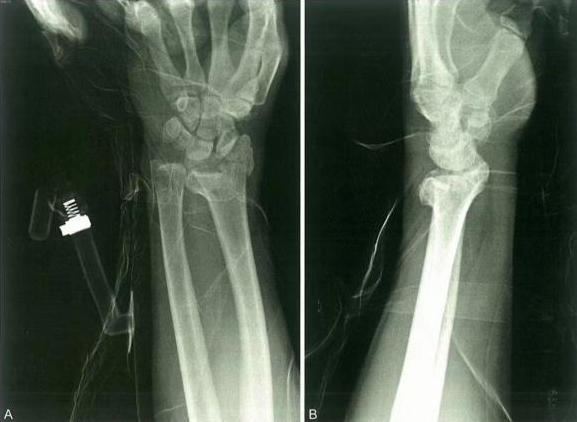

Случай ③